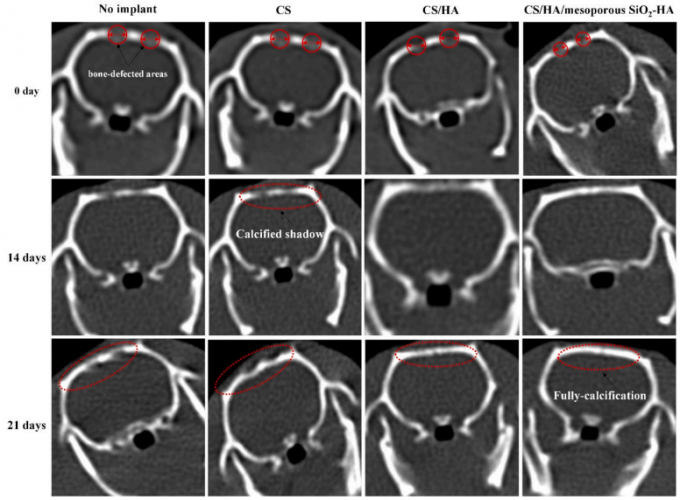

عضو هیأت علمی دانشکده مهندسی مواد دانشگاه صنعتی سهند بیان نمود: نتایج این دستاورد نشان میدهد این کامپوزیتها از ساختار و استحکام مناسبی جهت بازسازی استخوان برخوردار بوده و مطالعات درونتنی روی استخوان جمجمه موش صحرایی نشان دادند که بعد از ۲۱ روز، حدود ۹۰ درصد از استخوان آسیبدیده با بافت جدید جایگزین شده است. با استفاده از این نوع داربست، سرعتترمیم بدن موجود زنده تقریباً نه برابر بیشتر از حالت عادی بوده است.